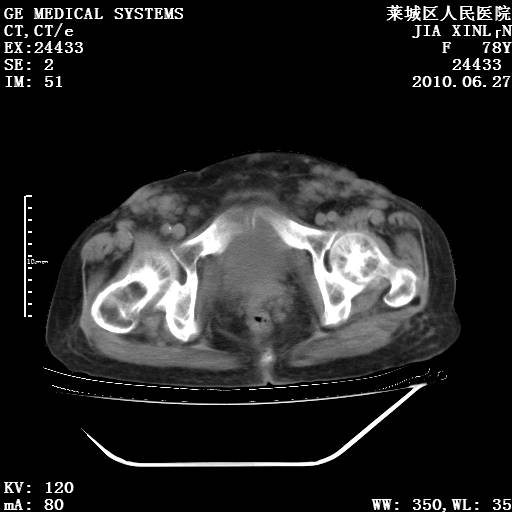

以下是引用胡宇在2010-7-2 19:11:00的发言:[br]神经纤维瘤的特点为:肿块呈多发性、数目不定,少的几个,多的可成百上千难以计数。小的如米粒,大的似拳头,甚至可达十数公斤以上。可松弛地悬挂于皮表,皱褶及松弛可致畸形明显。神经纤维瘤沿神经干的走向生长时呈念珠状,或蚯蚓块状形结节。此外神经纤维瘤皮肤可出现咖啡斑,大小不一,形如雀斑小点状,或大片状,分布与神经纤维瘤肿块的分布无关。肿瘤数目不多的患者,皮肤色素咖啡斑状沉着是纤维神经瘤的重要诊断之一。 本病多发于躯干,有时出现于四肢及面部,患者常合并许多疾病应予重视加以区别。 [br] [br] [br] [br]lyb999说 [br]